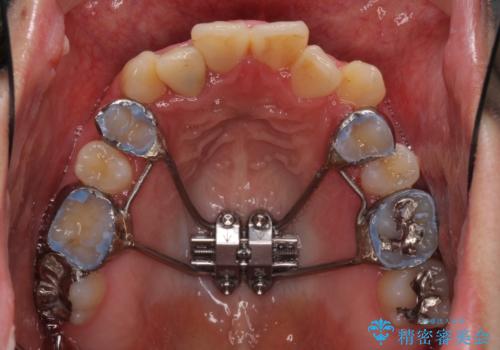

- 上下のデコボコと奥歯の咬みにくさを気にして来院された患者様です。

上顎骨の幅が下顎骨よりも小さいので、拡大装置により骨幅を広げて上下関係を改善し、その後インビザラインにて歯並びを整えることとしました。

上下の骨幅を改善したことで、スムーズに歯列矯正を行うことができました。